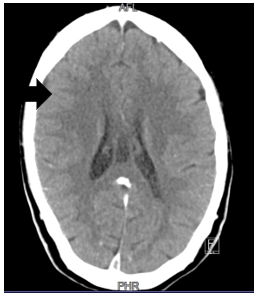

CT brain scan showed an extensive dural venous sinus thrombosis involving the posterior superior sagittal sinus, right transverse sinus, right sigmoid sinus and right proximal internal jugular vein (see Figure 1). No venous infarcts were noted. Retinal nerve fibre layer (RNFL) thickness was found to be markedly elevated bilaterally (right eye 217 microns; left eye 255 microns) on optical coherence tomography (OCT) (see Figure 2).

Figure 1: Contrasted CT brain from index patient reveals an empty delta sign in keeping with superior sagittal sinus thrombosis (black arrow)